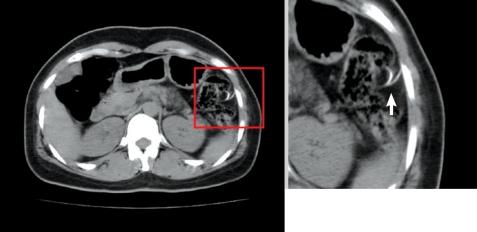

Foreign bodies in the gastrointestinal tract often cause serious complications, such as perforation, obstruction, abscess formation, or hemorrhage. This is a case in which a patient visited our hospital and complained of a vague lower abdominal pain that had been present for three months. She had an intrauterine device (IUD) inserted five years earlier. The abdominal X-ray, computed tomography and colonoscopy revealed that the IUD had penetrated into the descending colon. We tried to remove the IUD by colonoscopy but failed due to pain, so we removed the IUD surgically. Thus, we report a case in which a previously inserted IUD had penetrated into the descending colon and was surgically removed. We also present a brief review of the literature.